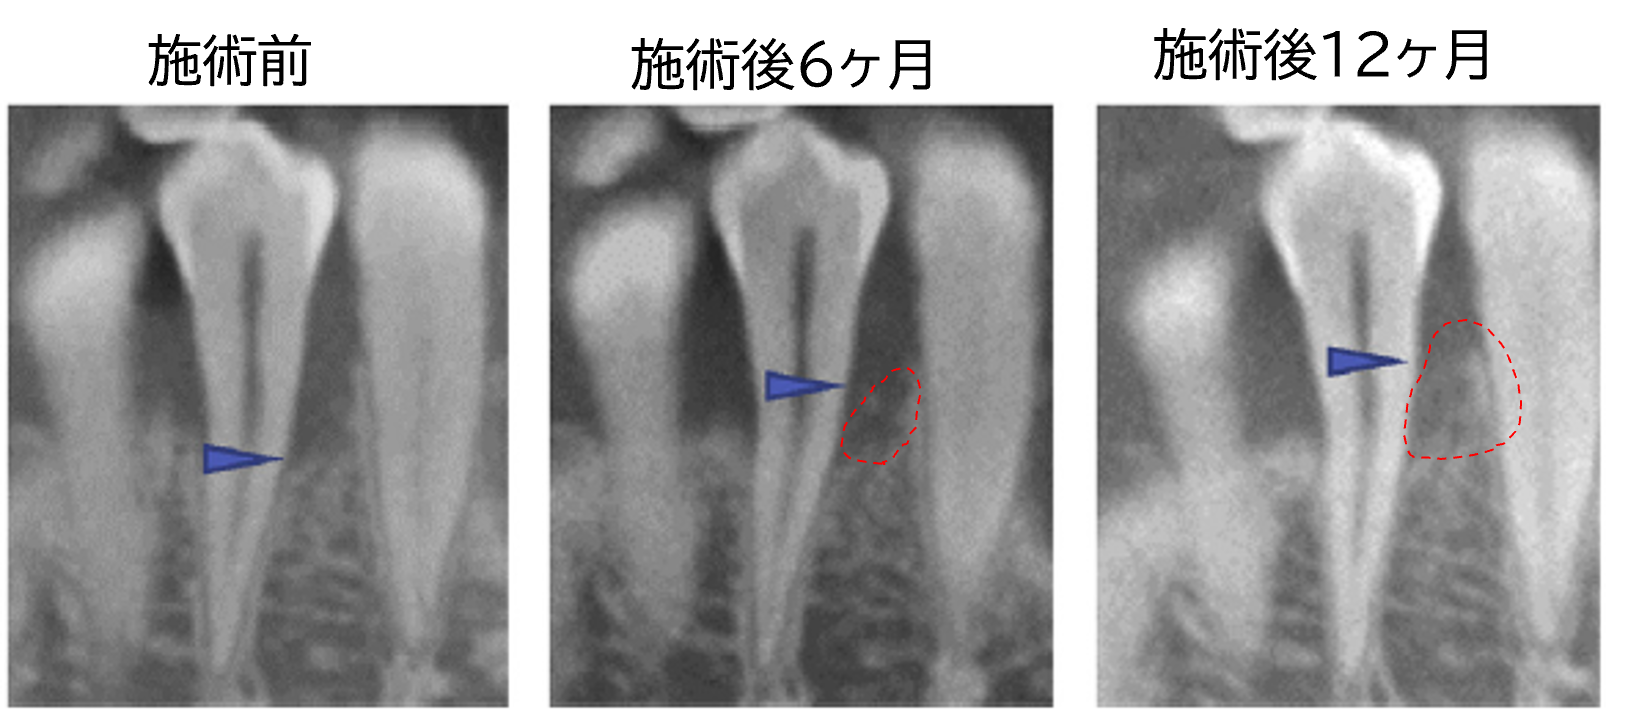

症例C|54歳男性

右下の第一大臼歯の頬側に、2面の骨が残る「2壁性骨欠損」が見られました。歯根膜細胞シートを移植したところ、6ヶ月後には骨の高さが4.6mm増加し、12ヶ月後にはさらに骨量が増加していることが確認されました。

※矢印先端は骨欠損部の最遠心端を示す。